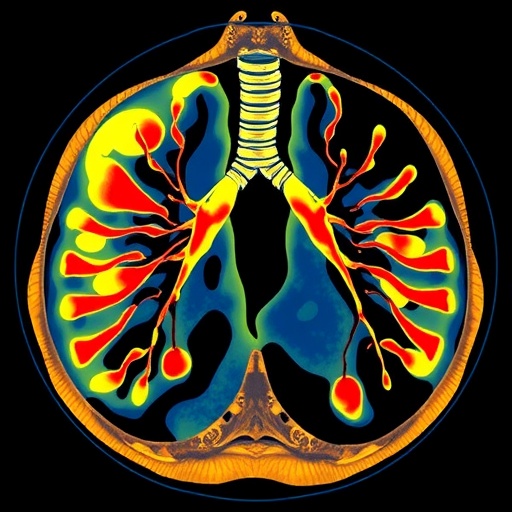

Recent advances in the field of radiomics—the comprehensive extraction of quantitative features from medical images—offer promising avenues to overcome these challenges. By harnessing high-throughput data derived from computed tomography (CT) scans, radiomics can reveal subtle imaging biomarkers that are often imperceptible to the human eye. These biomarkers, when combined with clinical indicators, may enable more precise and personalized predictions regarding LVI status in patients with invasive LUAD.

A pioneering study published in BMC Cancer has explored the integration of intratumoral and peritumoral CT radiomics features to develop predictive models for LVI in LUAD patients. The investigators analyzed CT images from a cohort of over 600 patients across two institutions, extracting an extensive array of more than 1,200 quantitative radiomic features from distinct tumor regions. This comprehensive approach allowed for a detailed morphological and textural characterization of both the tumor bulk and its surrounding microenvironment, which is critically implicated in tumor invasion dynamics.

The methodology employed in this study involved comprehensive feature extraction from high-resolution CT images, capturing a spectrum of matrix-based texture descriptors and wavelet transformations, which provide deep insights into tumor heterogeneity. Radiomic features related to shape, intensity, and texture likely reflect the complex biological processes underpinning tumor growth and vascular invasion, offering a quantitative surrogate marker unattainable through standard radiological interpretation.